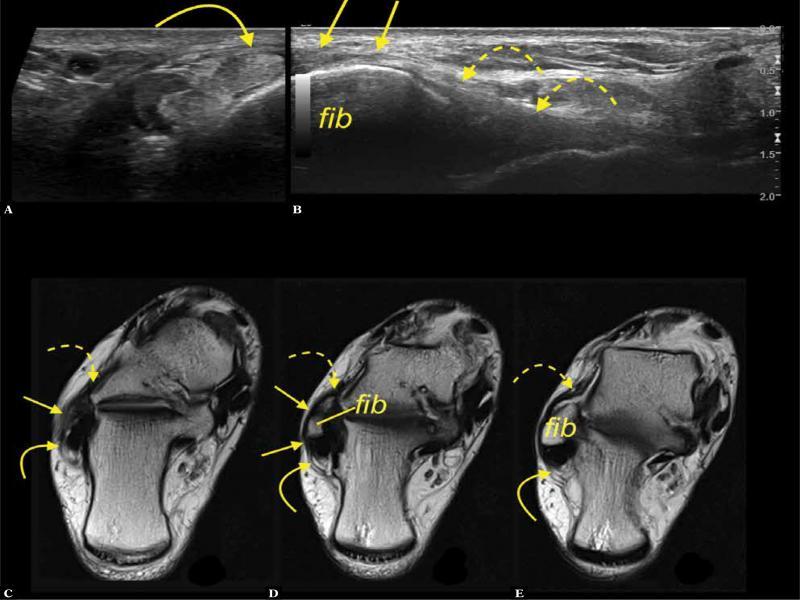

Fig. 5.

A 52-year-old patient presented with retromalleolar pain. A, B, C. transverse section on ultrasound. D. proton density-weighted transverse section. The interconnection (arrows) between the SPR (letter R) and IER (curved arrow) and ATFL. Fib – fibula

Superior peroneal retinaculum – peroneal tendon sheath

Connections to the PTS were found in 25.4% cases on US and 22.2% on MR. They were located inferior to the apex of the lateral malleolus (Fig. 6). The difference in the frequency of this connection between MR and US was the smallest among all the connections (difference 3.2%, p >0.05) (Tab. 1).

Fig. 6.

A 28-year-old patient with a clinical suspicion of an intraarticular free body in the ankle joint. A. transverse section at the level of the lateral malleolus (fib – fibula), SPR – curved arrow, connection to the PTS (straight arrow). B. oblique section along the calcaneofibular ligament (asterisk). C. coronal section at the level of the peroneal tubercle (t), PTS – dashed arrow, calcaneus – cal. D, E, F. MRI proton density-weighted axial sections